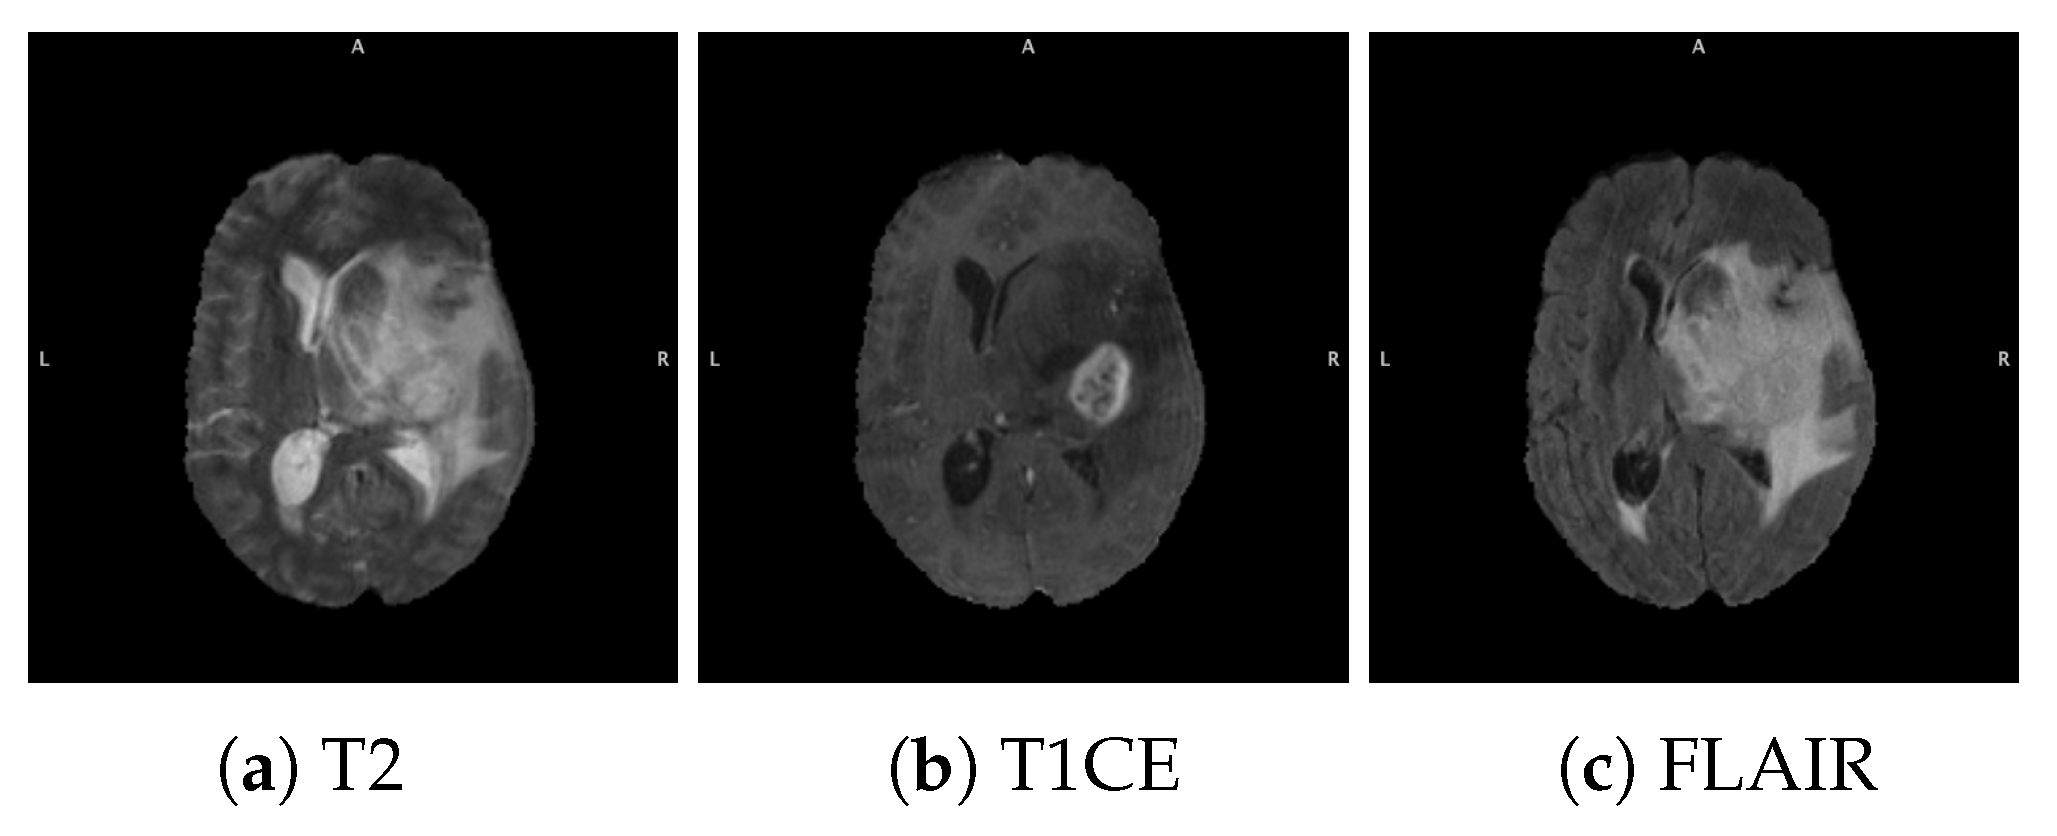

3.1. Data Acquisition and Preparation

3.1.1. BraTS Dataset

3.1.2. Data Acquisition

3.1.3. Data Pre-Processing and Augmentation

4.2. Combination of Multi-Sequence Data for Survival Prediction

4.2.1. Ensemble of Ensembles Using T1CE, T2, and FLAIR MRIs

4.2.2. Multi-Branch CNN Training with Multi-Sequence 3D MRIs